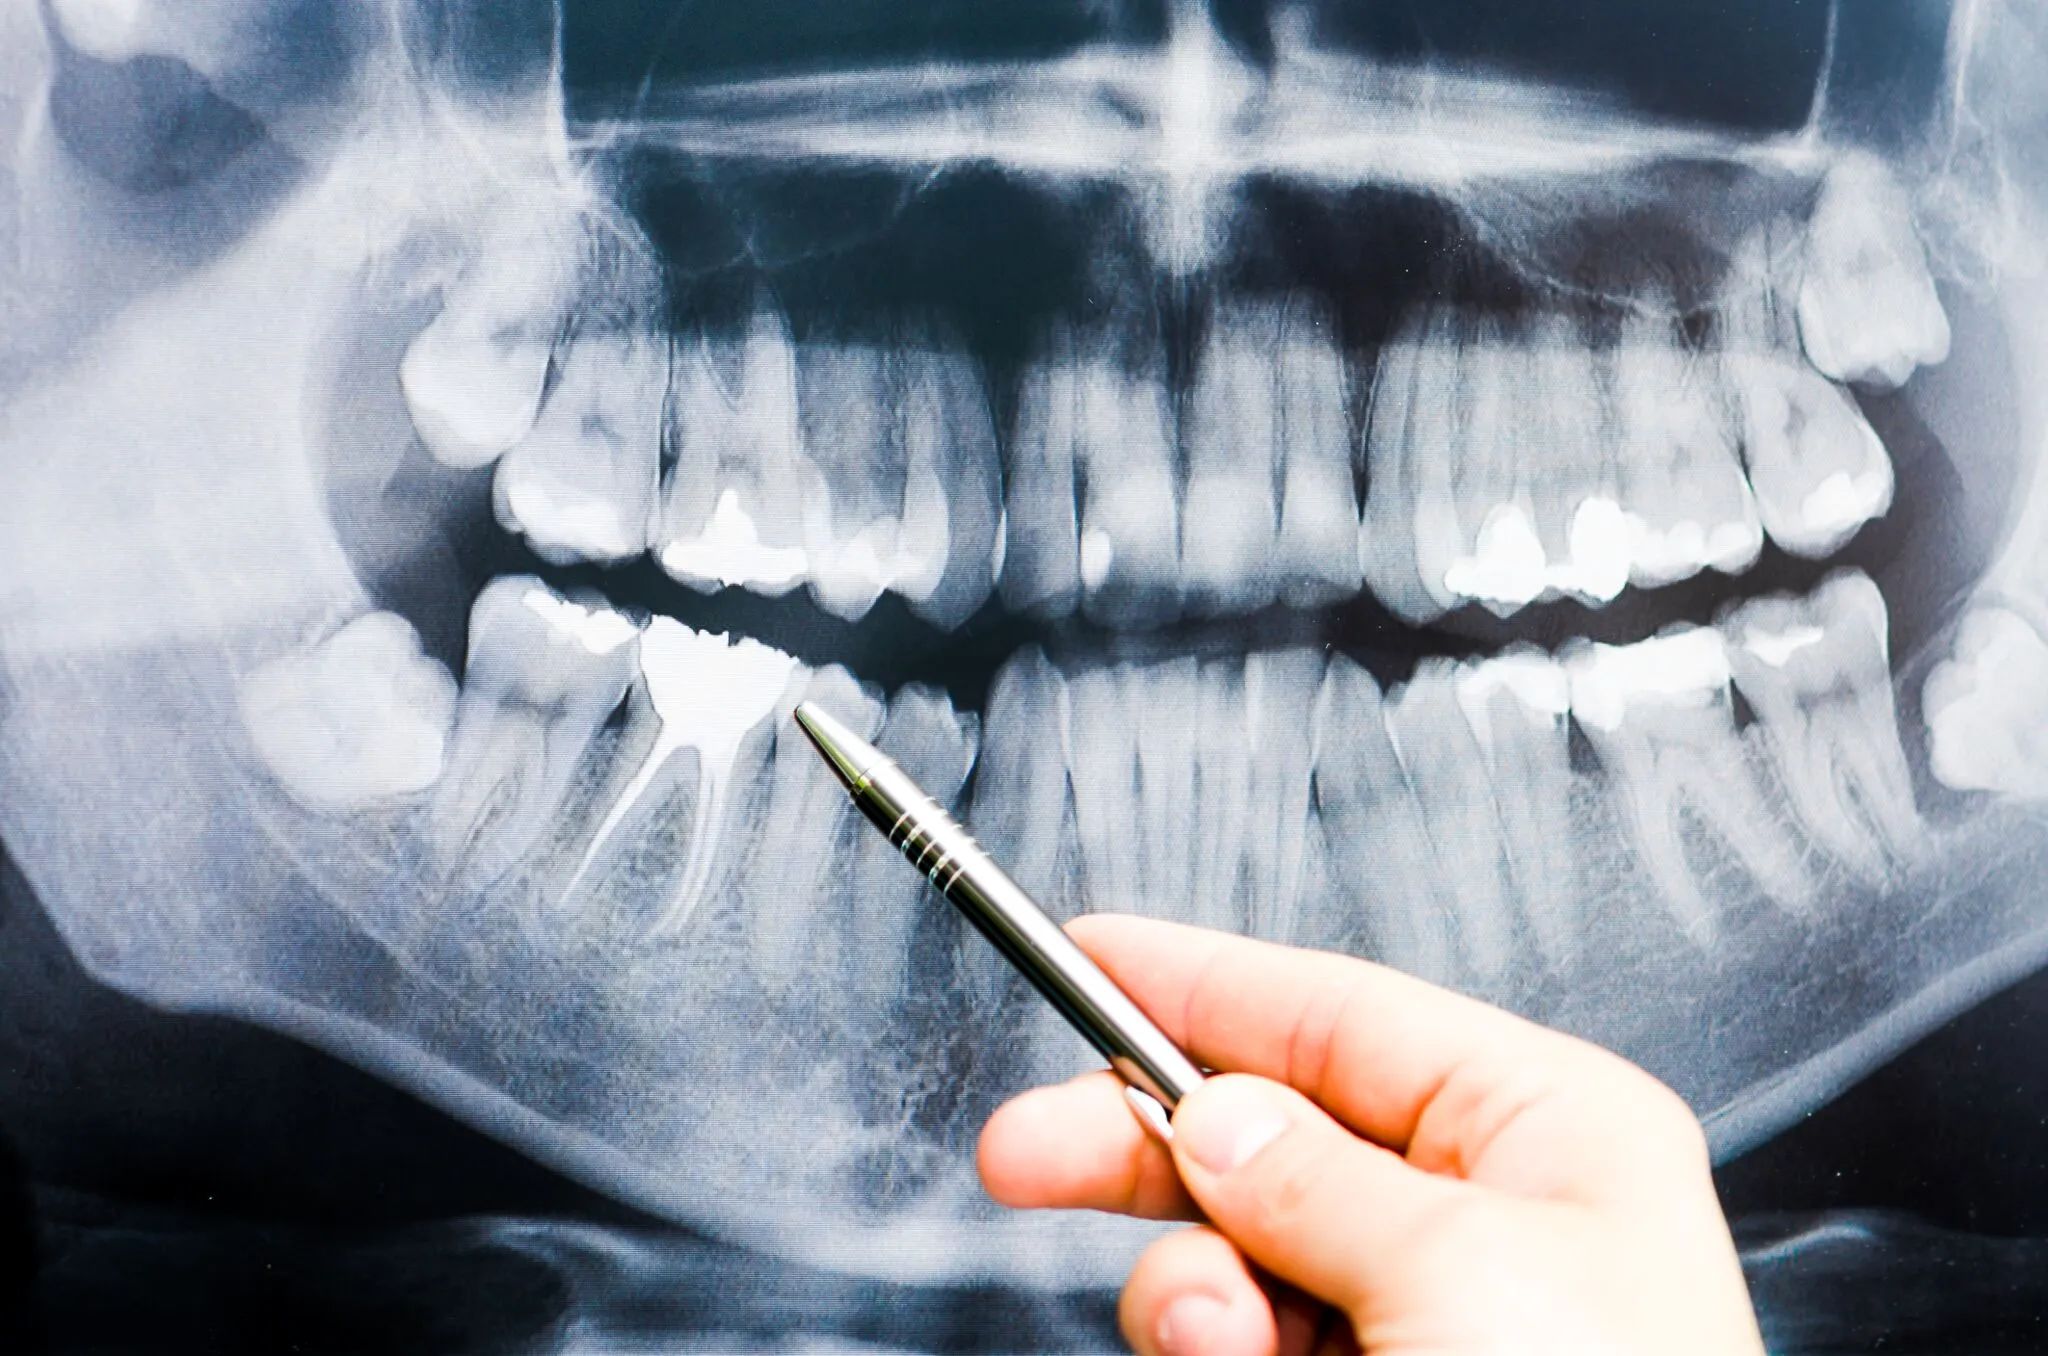

فاجعه خاموش در دهان ایرانیها

در روزهای اخیر گزارشی در سایتهای خبری مبنی بر وجود بیش از ۲۵۰ میلیون دندان پوسیده در دهان مردم ایران منتشر شد.

وضعیت بهداشت دهان و دندان در پایین ترین رتبه از سلامت کشور قرار دارد